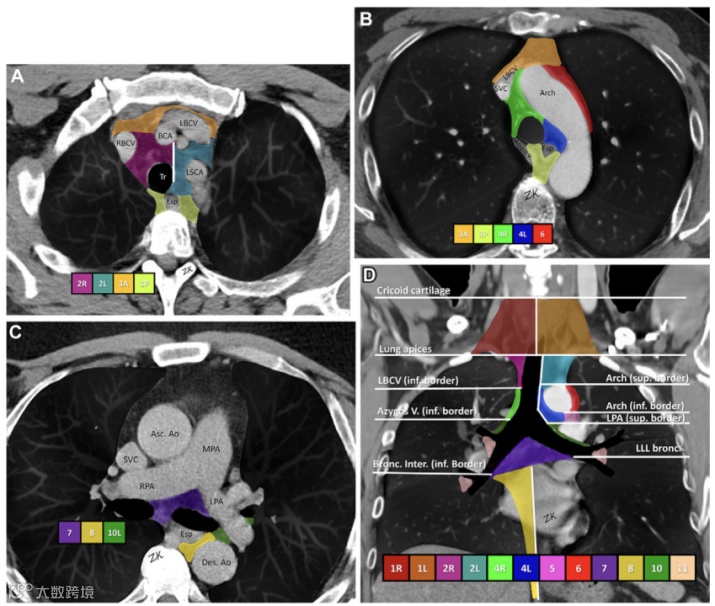

图5.纵膈淋巴结影像学示意图。

A-C为横断位;D为冠状位。气管的左侧壁,而非中线,作为2R和2L(A中的白线所示)以及4R和4L站点之间的边界(B中的绿色和蓝色区域所示)。Arch = aortic arch(主动脉弓),Asc. Ao = ascending aorta(升主动脉),Azygos V. = azygos vein(奇静脉),BCA = brachiocephalic artery(头臂动脉),Bronc. Inter. = bronchus intermedius(中间支气管),Des. Ao = descending aorta(降主动脉),Esp = esophagus(食管),LBCV = left brachiocephalic vein(左头臂静脉),LLL bronc = left lower lobe bronchus(左下叶支气管),LPA = left pulmonary artery(左肺动脉),LSCA = left subclavian artery(左锁骨下动脉),MPA = main pulmonary artery(主肺动脉),RBCV = right brachiocephalic vein(右头臂静脉),RPA = right pulmonary artery(右肺动脉),SVC = superior vena cava(上腔静脉),Tr = trachea(气管)。